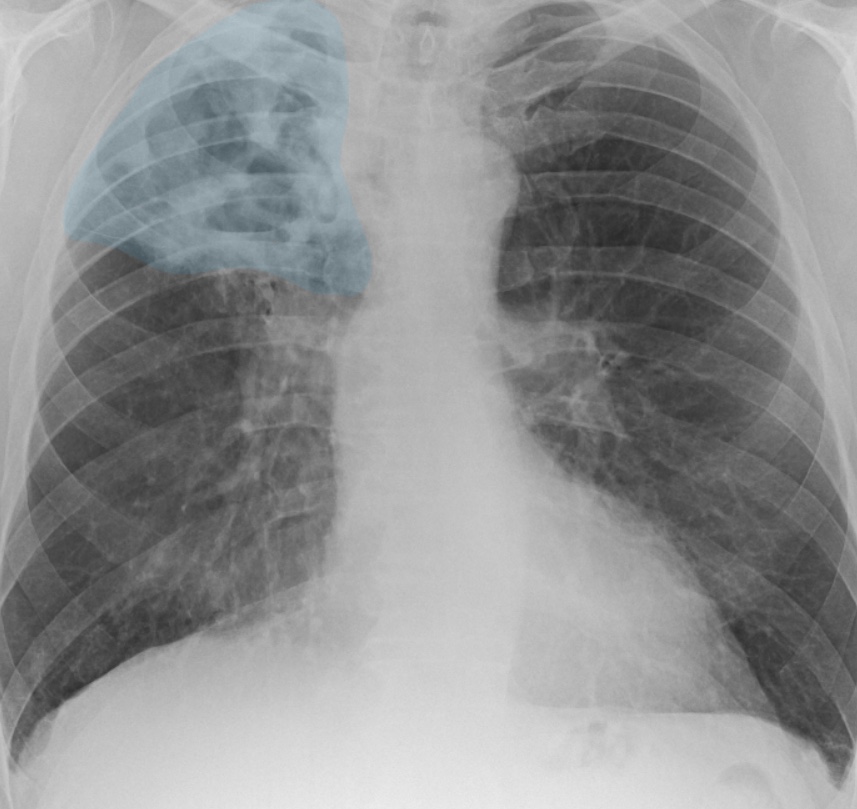

Chest X-rays are the most frequently requested imaging investigation worldwide. A variety of health care professionals including doctors, nurses and radiographers are required to review chest X-rays. Curated by expert thoracic radiologists, this package aims to provide an introduction to chest X-ray interpretation.

Tuberculosis (TB) is a highly infectious disease caused by bacteria, and its diagnosis relies on chest X-rays. This package helps explain the pathogenesis of TB, its appearance on radiographs and offers guidance on features to consider that differentiate latent and active TB infection